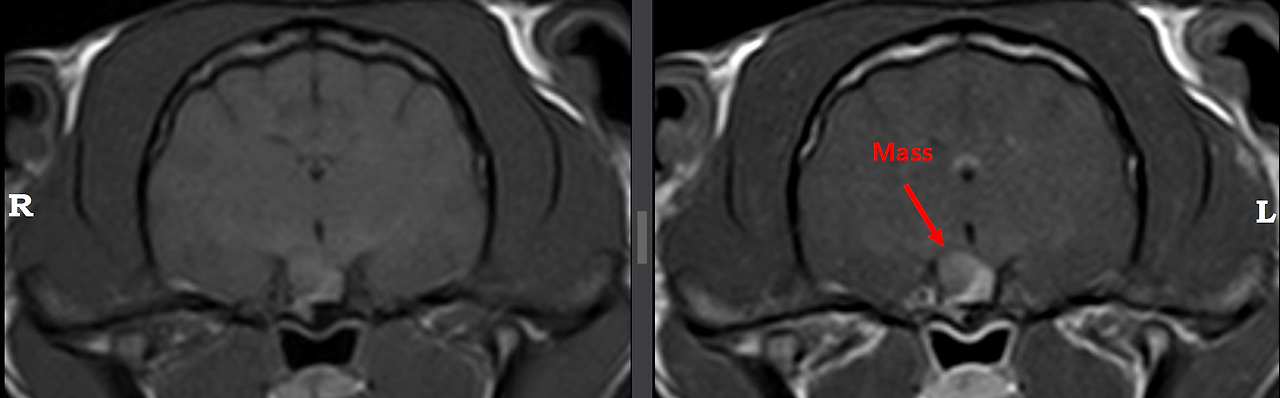

촬영이 끝나고, 후배와 같이 영상을 돌려 봤는데, 정말 있었다. 오톨이 뇌의 뇌하수체 부분에 종양이 보였다. 조영제를 투여하자 하얗고 뚜렷하게 드러난 종양. 너 거기에 언제부터 숨어있었니.

고양이 뇌하수체 종양 MRI는 좀처럼 만나기 어려운 케이스이고, 이 후배에게나 나에게나 의미 있는 공부 영상이 될 터였다.

조영제 주입 시 뚜렷하게 드러나는 종양